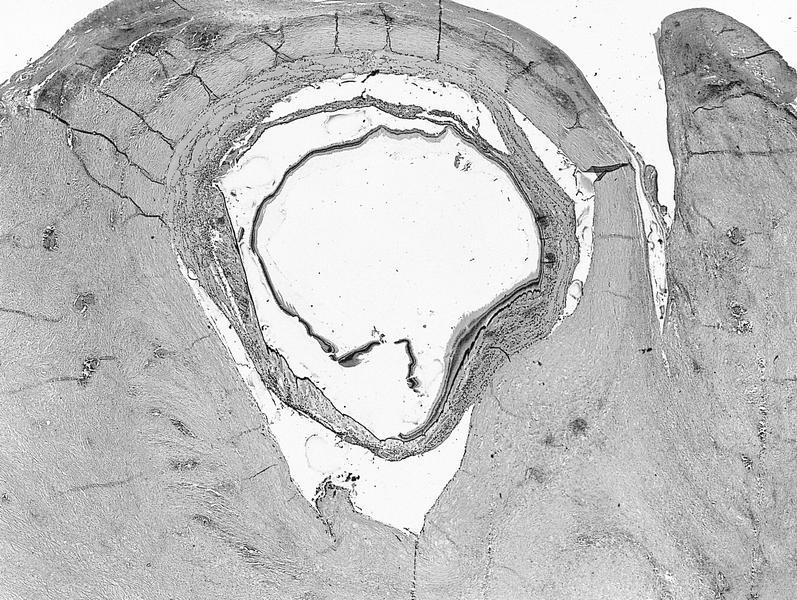

Whole mount images

AFIP images

Whole mount images

AFIP images